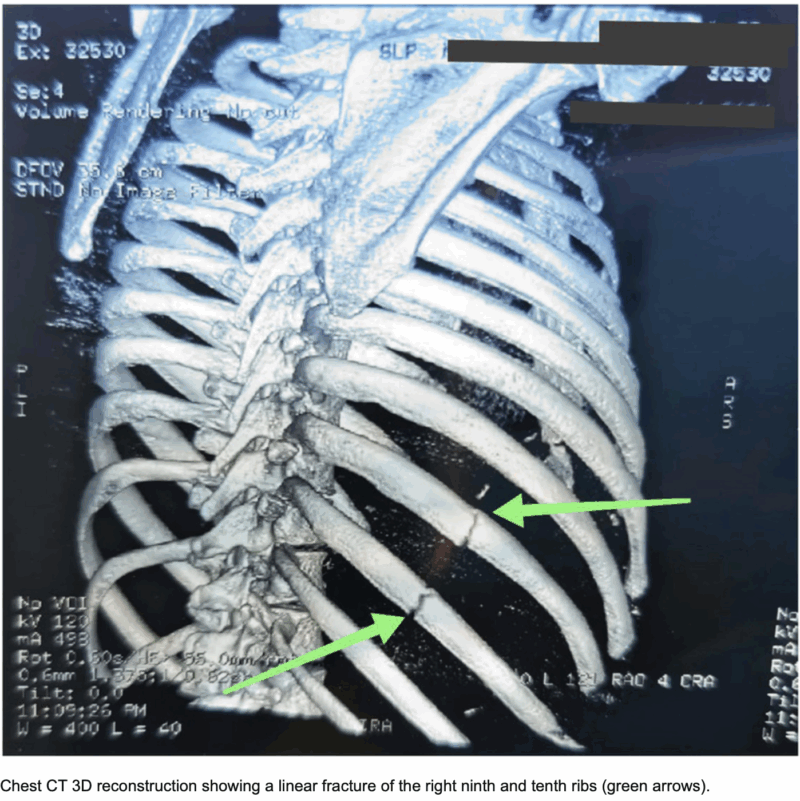

骨折した部位が明瞭に描出されています.

引用元:Alhatemi AQM. Rib fracture secondary to cough‐induced trauma. Clin Case Rep. 2024. 12.

11時半すぎに救急車が到着しました. 頬と胸をぶつけたようでした. 特にほほの骨(頬骨きょうこつ)と9, 10, 11番目の肋骨を圧すと痛みが強いので, 骨折を疑って頭と胸のCTを撮像するようにオーダーしました. CTを確認しましたが, 頬骨に骨折はありませんでした. また, 肋骨にも骨折はありませんでした.

肋骨は弯曲しているので, 骨折部にズレがない骨折だと, X線写真の角度によっては骨折が写らないことがあります. 骨折を見逃さないようにするためには, CTを撮像して, 3−D再構築画像として確認する必要があります. 特に, 交通事故や労災事故では, 骨折を見逃すと, 後々問題となるので, 必ずCTを撮像することにしています.